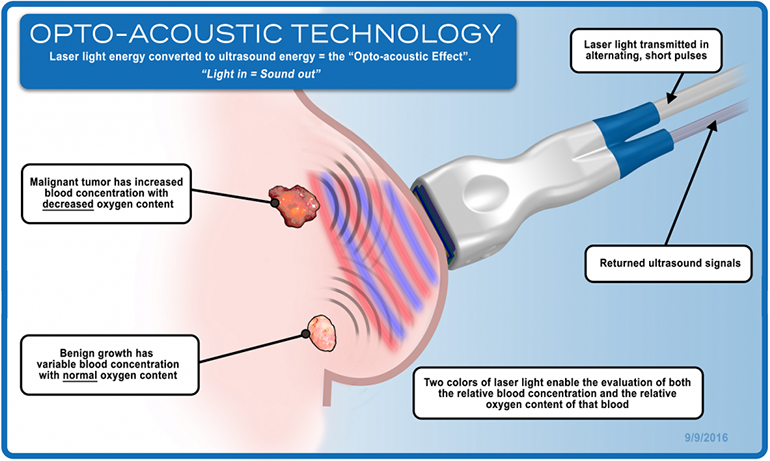

The Imagio breast imaging system was designed and is being studied to identify two functional hallmarks of cancer: the presence of abnormal blood vessels (tumor angiogenesis) and the relative reduction in oxygen content of blood that occurs in cancer compared to benign masses and normal tissues. The technology is CE marked in Europe and the subject of a U.S. PMA filing with the FDA.